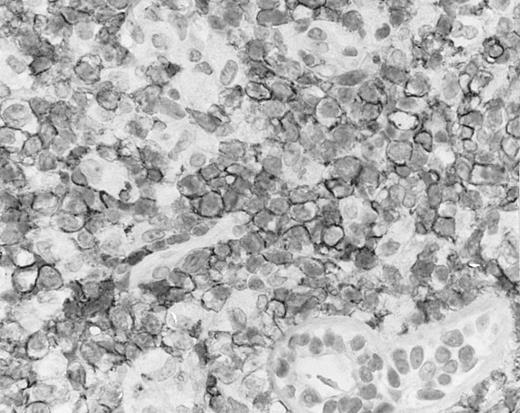

Cutaneous nasal-type NK/T-cell lymphoma (case no. 34). (A) This biopsy was initially misinterpreted as vasculitic lesion because of the small size of the lymphoid cells and the minimal cellular atypia. (B) Large numbers of lymphoid cells in the skin show positive labeling for EBERs on in situ hybridization. The sweat gland in the left field is negative.

Cutaneous nasal-type NK/T-cell lymphoma, with the lymphoma cells showing cell membrane staining for CD56 on paraffin section. The sweat gland in the lower field is not stained.

By definition, the neoplastic cells showed CD56 expression (Fig 4). All except 2 cases (cases no. 7 and 12) reacted with the polyclonal CD3ε antibody on paraffin sections, but both CD3ε− cases were immunoreactive for CD43 and CD45RO. Among 18 cases in which frozen tissue was available for analysis, all were CD2+; 1 case each stained for CD3/Leu4 (weak staining), CD7, and CD8 and all cases were negative for CD4, CD5, CD16, CD57, and B-lineage markers. Thirty-two (94.1%) cases showed labeling for EBERs in practically all neoplastic cells (Fig 3B); 2 cases were negative.